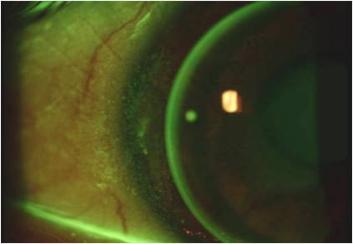

Zoals op de afbeelding hiernonder te zien is, wordt de hyperaemie veroorzaakt

door de perifere staining (op 3 en 9 uur) in beide ogen. Maar waardoor ontstaat die

3 en 9 uur staining? De tetracurves zaten misschien niet altijd even comfortabel,

maar veroorzaakten geen fysiologische problemen. In mijn overtuiging moest de

oorzaak gezocht worden in de diameter of het materiaal. Stap voor stap heb ik

Uiteindelijk kwam er een oplossing uit een onverwachte hoek. En zie het resultaat

in de figuur hieronder. De hyperaemie en staining zijn verdwenen, het comfort en

de visus zijn zeer goed. Maar wat voor lens zit er nu op het oog? Uit het fluorbeeld

is af te leiden dat de edge vrij groot is en een stuk groter dan bij de eerste paslens.